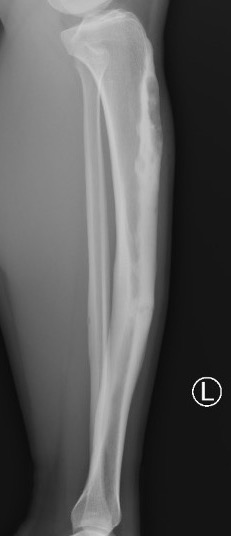

X-ray

Multiple small radiolucent lesions surrounded by sclerosis

Thickened cortex

Doesn't progress on xray

Most common anterior cortex of tibia

Soap-bubble appearance

Eccentrically located

- well circumscribed

- slightly expansile

- cortical thickening

- little or no periosteal reaction